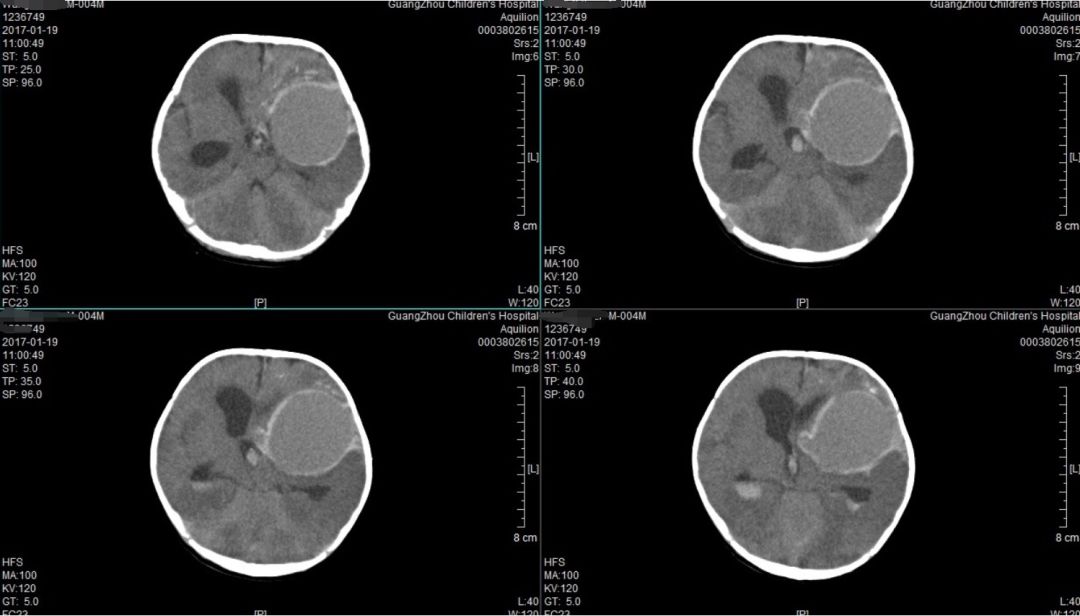

正常头颅ct平扫图片

头颅ct扫描定位线图片

头颅ct扫描基线图解